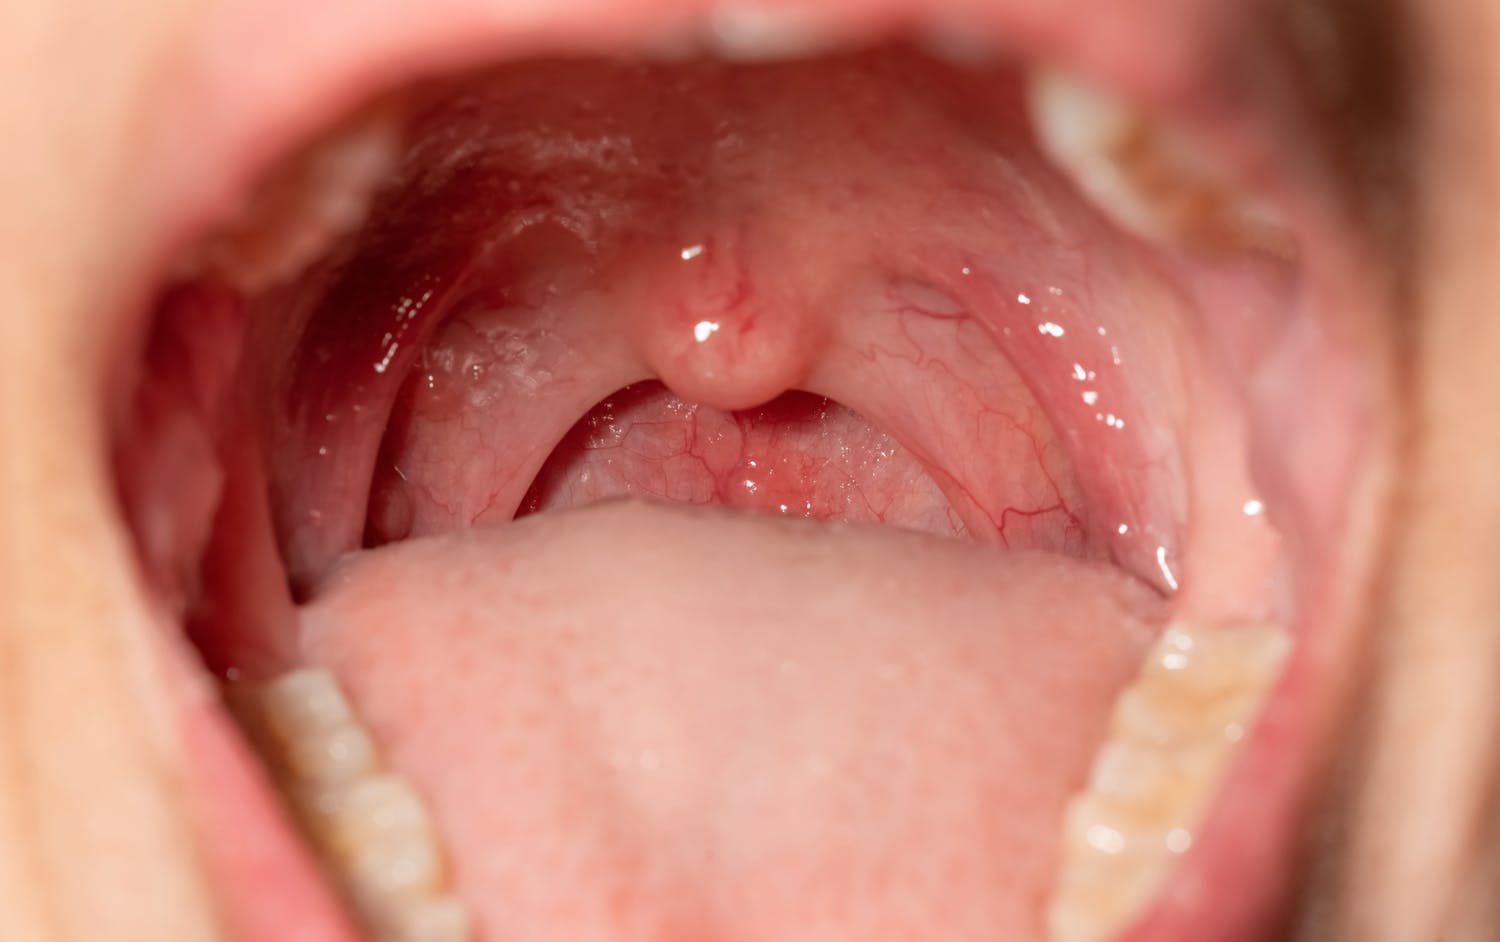

Syphilis, LGV, gonorrhée, chlamydias, condylomes… les infections sexuellement transmissibles (IST, anciennement MST) sont de retour alors que certaines avaient pratiquement disparu. Elles touchent aujourd’hui un public mal informé. Quelles sont les raisons ? Comment mieux s’en protéger ? Réponses. Syphilis, LGV, gonorrhée, chlamydias,